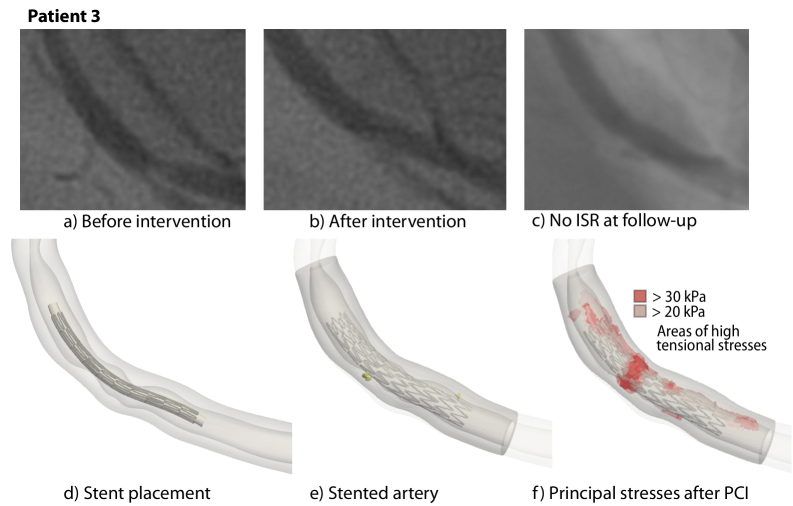

Appendix D Stent placement and correspondence to angiography data

In the following, we compare the simulation results of Patient 1, 2, 3, and 4 to the angiography imaging data, see Fig. 11, 12, 13, and 14, respectively. We select single frames during the diastole from the respective angiography data. For each patient, Subfigures a) and d) show the configuration before the intervention. Subfigures b) and e) show the angiography image after the intervention and the simulated stented artery. Subfigures c) and f) compare the follow-up angiography with the maximum stresses after the intervention.

Figure 13: Stent placement and corresponding angiography data for Patient 3

Figure 17: First principal stress values in selected cross-sections during and after PCI; Patient 3. The plaque morphology is shown in the CCTA cross-sections and in the model. The stent cross-section is shown as black dots. Ca: Calcification.

Patient 3 shows no significant calcifications; the lesion mainly comprises fibrous tissue. We observe the highest stresses during the maximum balloon inflation in the location of the most severe stenosis. However, the remaining stresses after the balloon withdrawal are reduced drastically and more evenly distributed in the tissue than in the lesions with calcifications.

Refer to caption